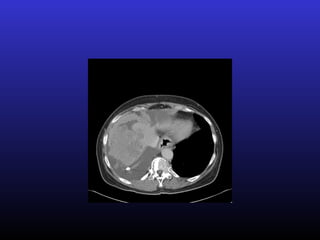

• #12 Colorectal CA with liver met – left lobe of liver – visceral pain